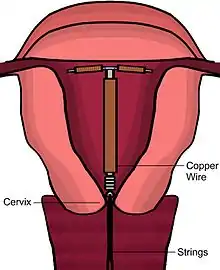

Device description

There are a number of models of copper IUDs available around the world. Most copper devices consist of a plastic core that is wrapped in a copper wire.[11] Many of the devices have a T-shape similar to the hormonal IUD. However, there are "frameless" copper IUDs available as well. ParaGard is the only model currently available in the United States. At least three copper IUD models are available in Canada, two of which are slimmer T-shape versions used for women who have not had children. Early copper IUDs had copper around only the vertical stem, but more recent models have copper sleeves wrapped around the horizontal arms as well, increasing effectiveness.[35]

Some newer models also contain a silver core instead of a plastic core to delay copper fragmentation as well as increase the lifespan of the device. The lifespan of the devices range from 3 years to 10 years; however, some studies have demonstrated that the TCu 380A may be effective through 12 years.[25]

Immediately prior to insertion, the clinician will perform a pelvic exam to determine the position of the uterus.[20] After the pelvic exam, the vagina is held open with a speculum.[36] A tenaculum is used to steady the cervix and uterus.[36] Uterine sounding may be used to measure the length and direction of the cervical canal and uterus in order to decrease the risk of uterine perforation.[37] The IUD is placed using a narrow tube, which is inserted through the cervix into the uterus. Short monofilament plastic/nylon strings hang down from the uterus into the vagina. The clinician will trim the threads so that they only protrude 3 to 4 cm out of the cervix and remain in the upper vagina. The strings allow the patient or clinician to periodically check to ensure the IUD is still in place and to enable easy removal of the device.[20]